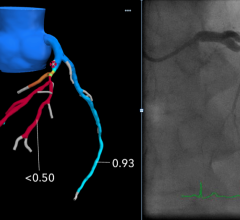

News | CT Angiography (CTA)

August 6, 2019 — When used with a common heart scan, machine learning, a type of artificial intelligence (AI), does…